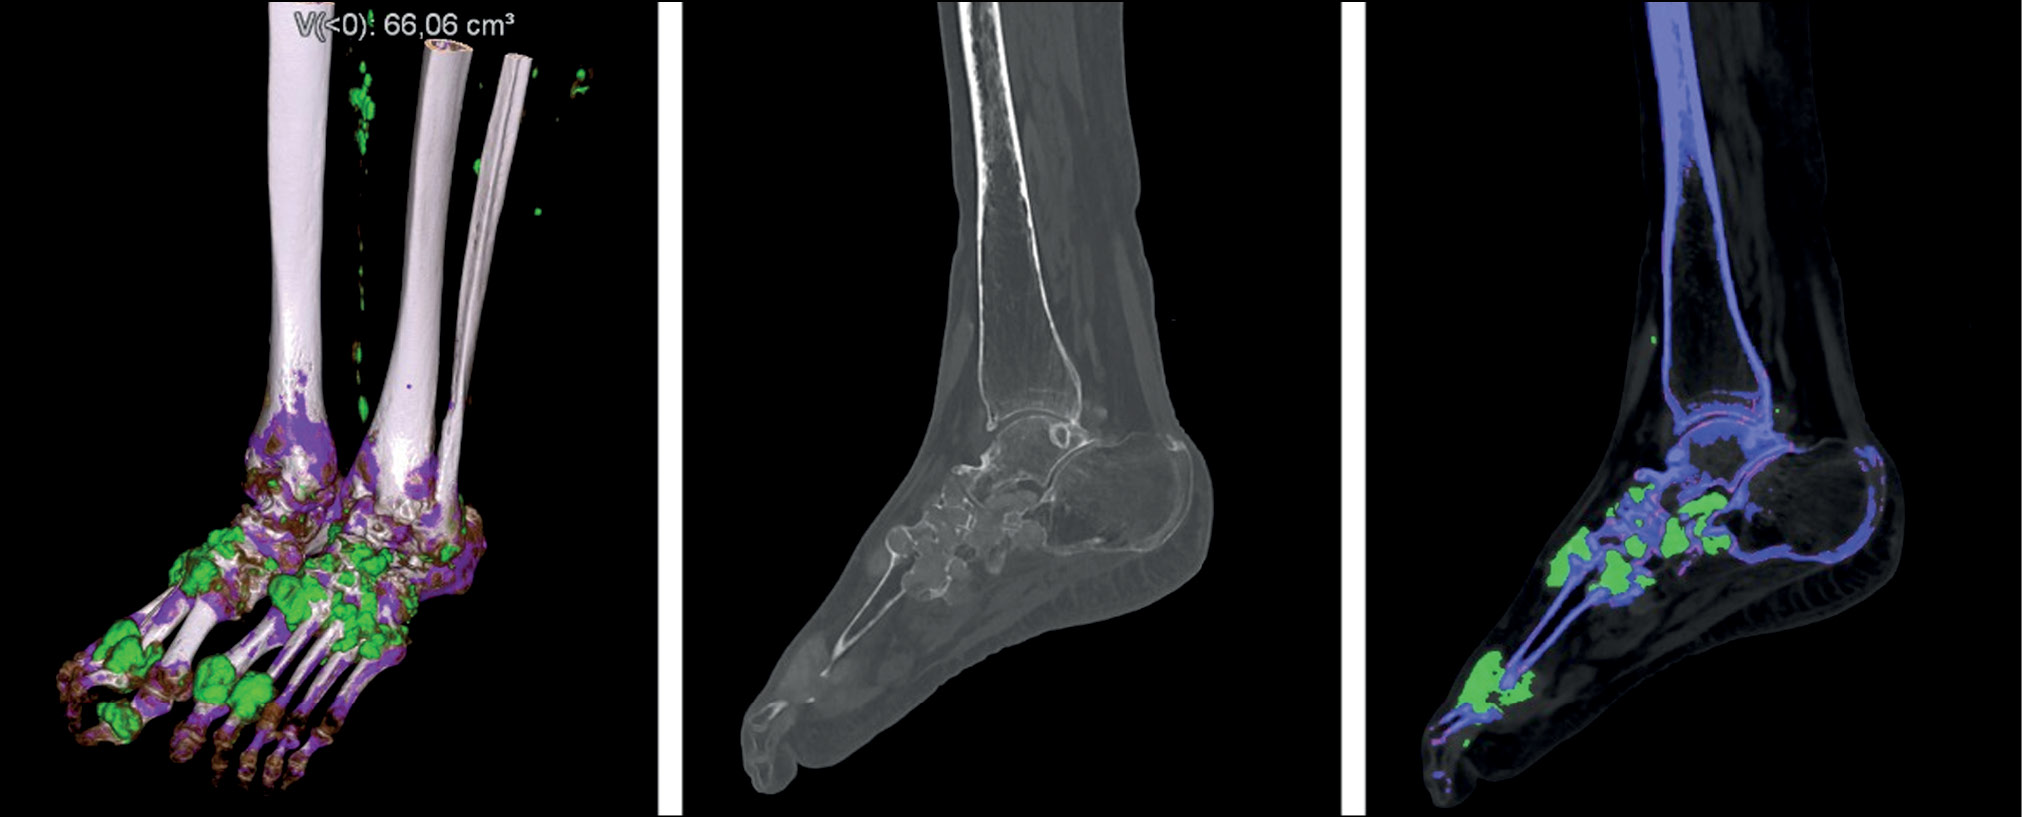

The role of DECT in the diagnosis of calcium pyrophosphate crystal deposition disease is unclear. Calcium-containing deposits will be colored blue on color-coded images obtained with DECT in the dual-energy gout class, allowing them to be distinguished from monosodium urate-containing deposits. The cortical bone is color-coded similarly to calcium pyrophosphate and hydroxyapatite deposits because of its high calcium concentration (Fig. 4).

Fig. 4. Color-coded dual-energy coronal and sagittal images (left knee joint). Calcification of the medial meniscus (dual-energy computed tomography findings of the Medical Research and Education Center of the Lomonosov Moscow State University).